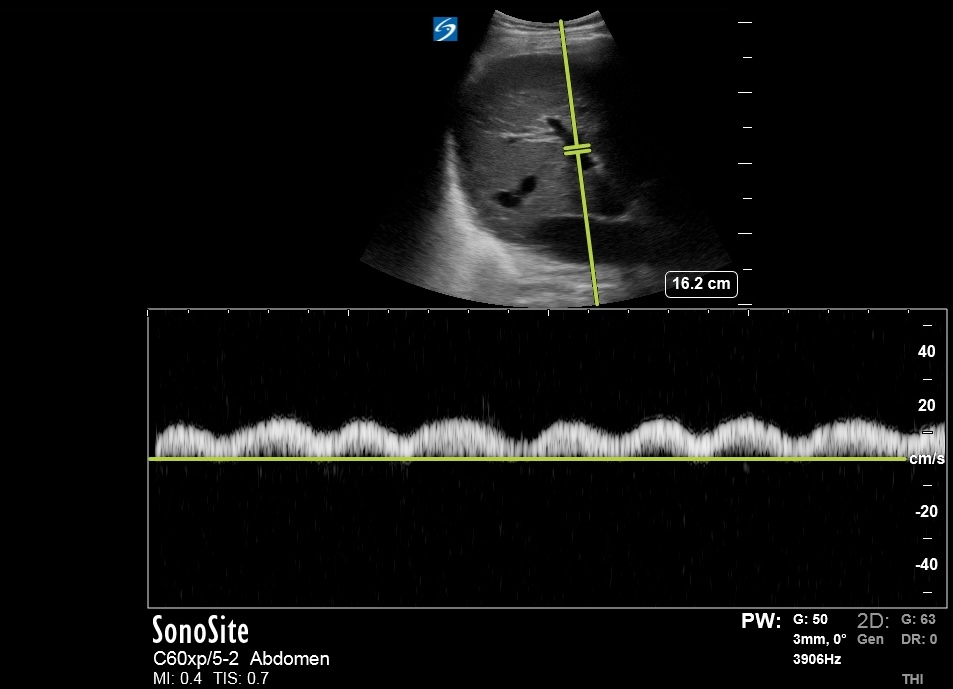

Bedside US done ~2 hours prior to RHC:

Bedside US done ~2 hours prior to RHC:

Another HV Doppler:

S Wave reversal better seen here. Thanks to @ArgaizR

S Wave reversal better seen here. Thanks to @ArgaizR